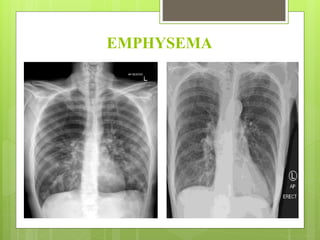

EMPHYSEMA

 Emphysema is a lung condition that causes shortness of

lungs (alveoli) are damaged.